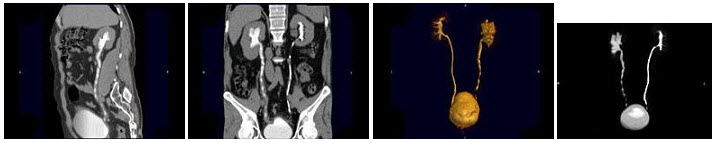

223、多项选择题

男,65岁,反复发作的下腹部疼痛向会阴部放射伴血尿1年余,CT如图所示,下列说法正确的是()

A.左肾位置形态无异常

B.右肾窝内未见肾影,于盆腔入口处L5~S1水平见异位肾影

C.左侧输尿管在膀胱入口处可见一高密度结石影

D.左侧输尿管扩张

E.考虑为先天性异位肾合并对侧输尿管下端结石